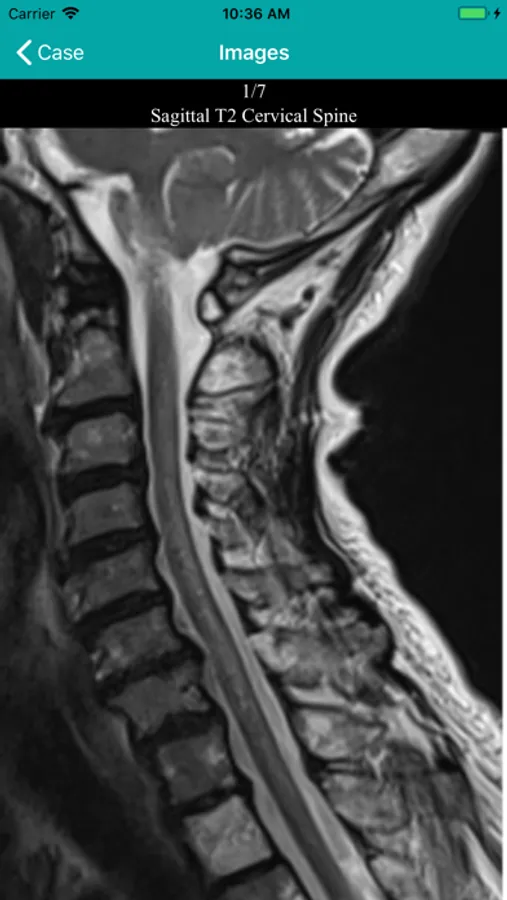

Discover Roentgen 2023 Screenshots